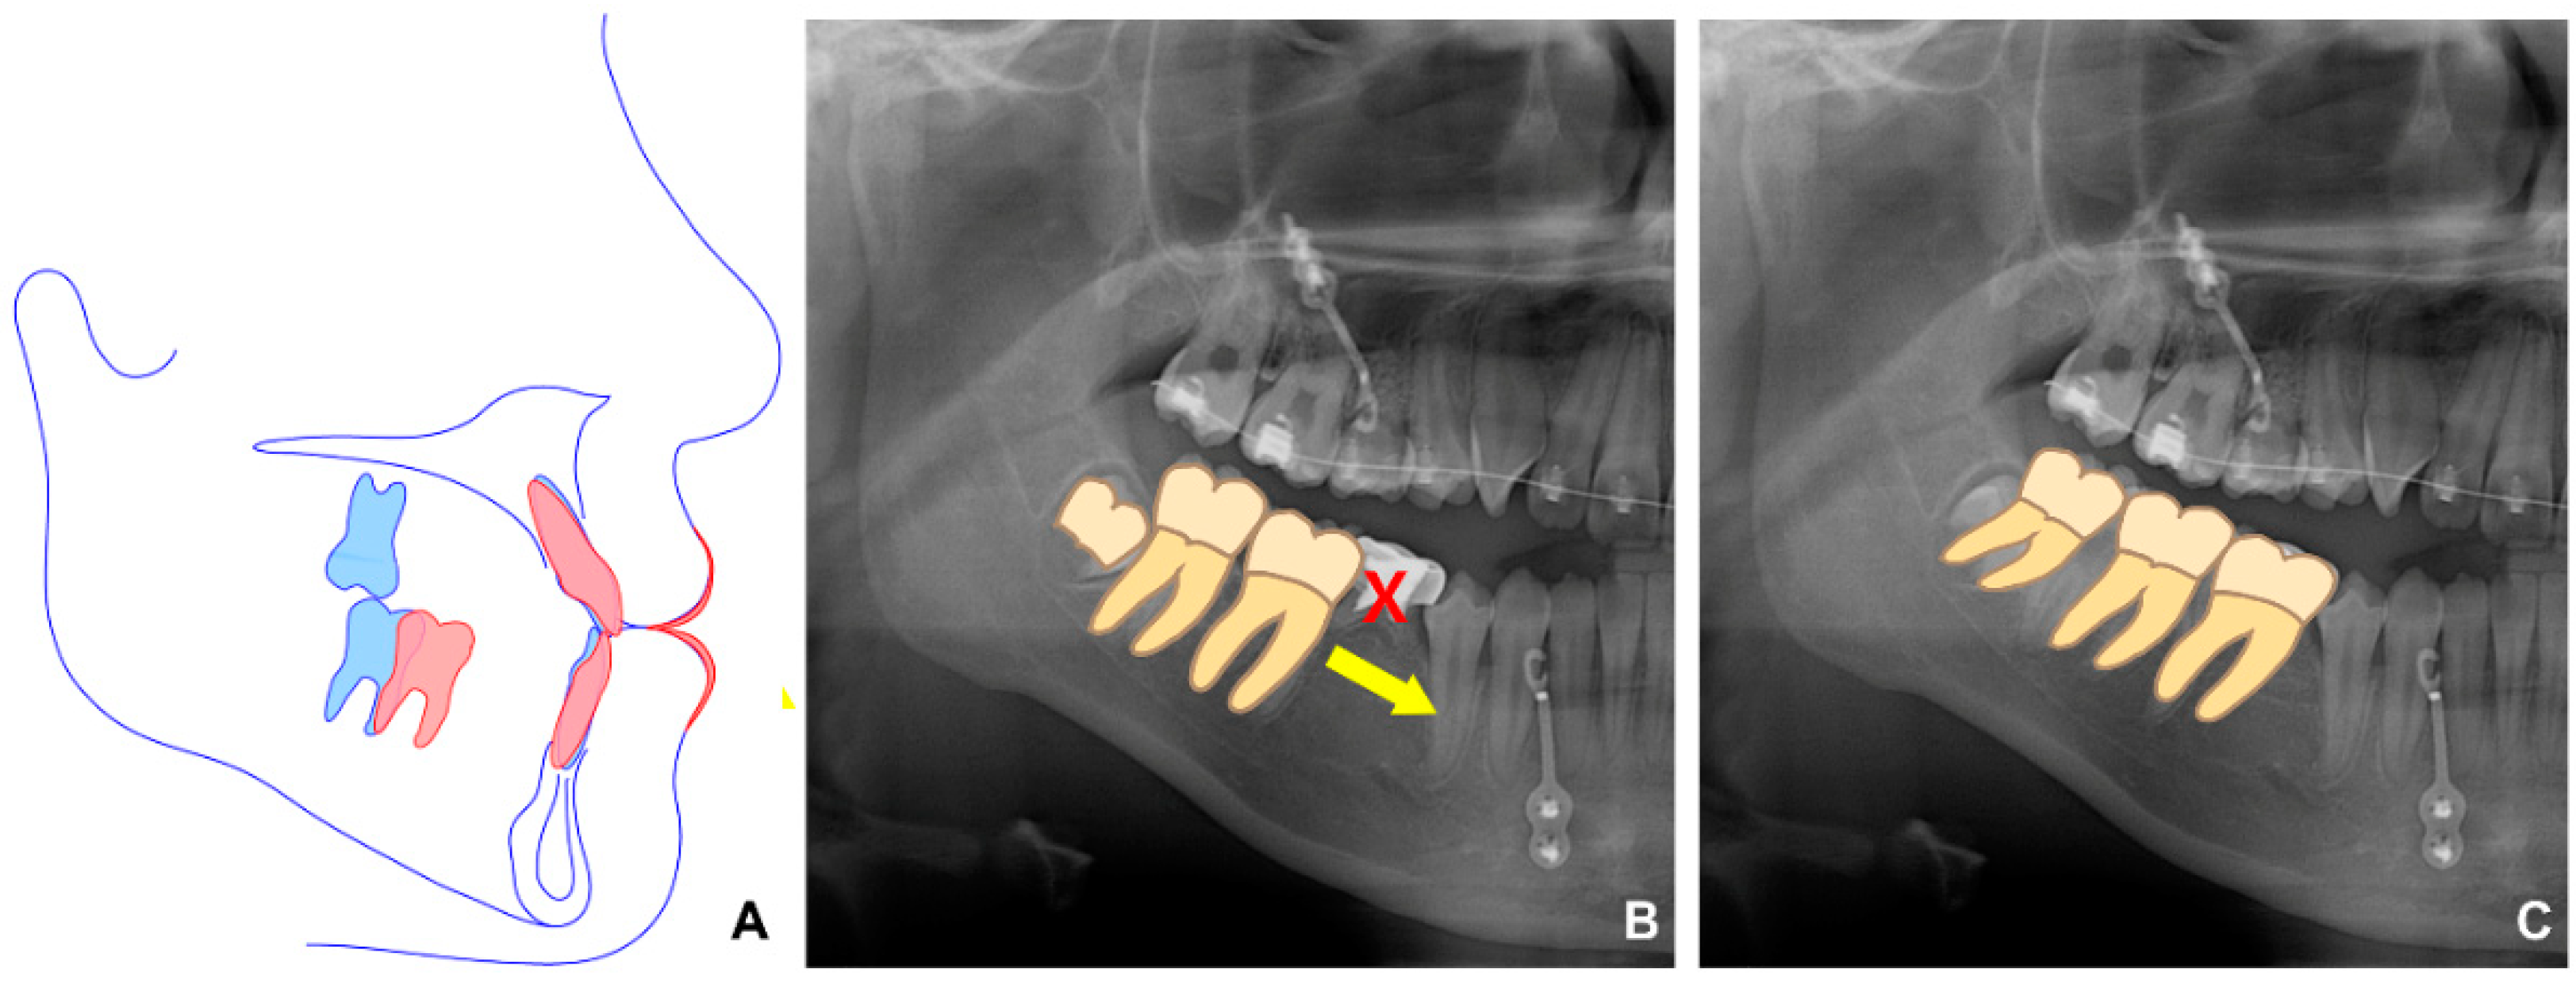

In the second phase, after bonding the fixed appliance to the maxillary and mandibular dentition, treatment started with the following goals: proclining maxillary incisors and closing most of the extraction space of the extracted mandibular primary tooth through protraction of the right molar, which induced spontaneous eruption of the right third molar (Figure 4). In addition, to improve the midline, the mandibular left third molar was extracted, and the mandibular dentition was moved to the left.

Figure 4. Schematic diagram related to protraction of the mandibular right posterior teeth. (A) Virtual treatment objective image. Blue and red lines are before and after treatment, respectively. (B) The protraction of the mandibular right first and second molars to the position where the right primary second molar was extracted. The yellow arrow represents the direction of tooth movement. X indicates extracted tooth. (C) Eruption of the mandibular third molar to the natural occlusal plane because of the anterior movement of the mandibular right molars.